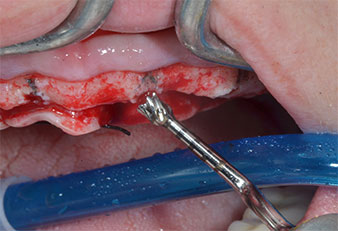

Пиезоелектрически инструмент с диамантено покритие с форма на пламък (Piezomed I1) e използван за маркиране на позициите на имплантите и за пилотна подготовка (Фиг. 3). Препарацията беше извършена с внимателни вертикални движения, с намалена мощност, пълна иригация и лек натиск (под 300 g) След това се приложи пилотен инструмент (Piezomed I2A/ I2P) за първоначално увеличение на диаметъра на имплантното ложе с 2 mm (Фиг. 4), последвано от 3 mm разширение (Фиг. 5)

Ултразву��ов пилотен накрайник за Piezomed

Фиг. 3 Препарацията с ултразвуков пилотен накрайник I1 се извършва с движение нагоре-надолу, успоредно с дългата ос на работната част.